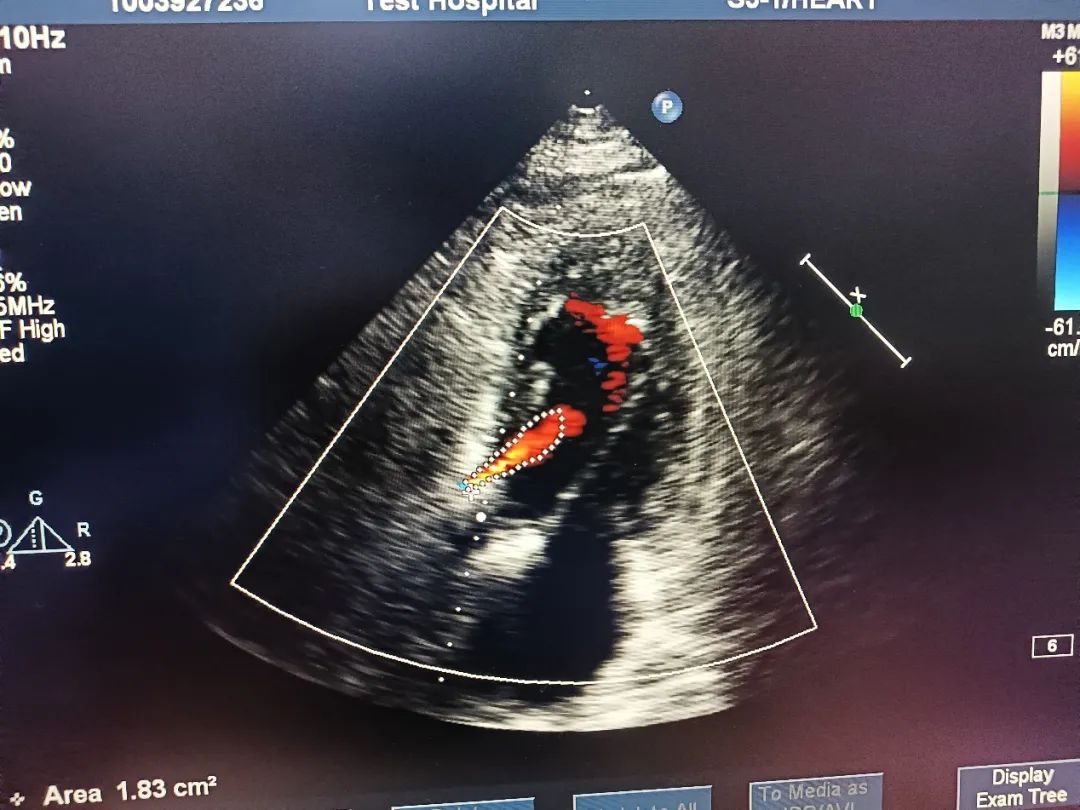

术中超声

超声结果示:微量瓣周漏,主动脉瓣口峰值流速为1.98 m/s,峰值跨瓣压差为 16 mmHg